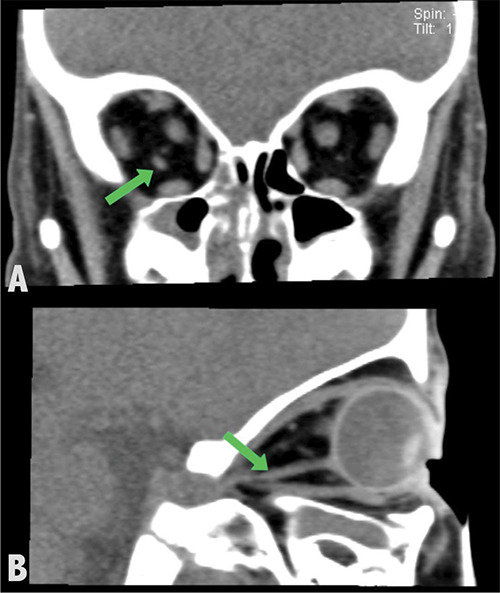

教学要点:副眼外肌是少见的眶内先天性结构,可引起复视和限制性斜视。

Teaching point: Accessory extraocular muscles are rare intraorbital congenital structures that can cause diplopia and restrictive strabismus.